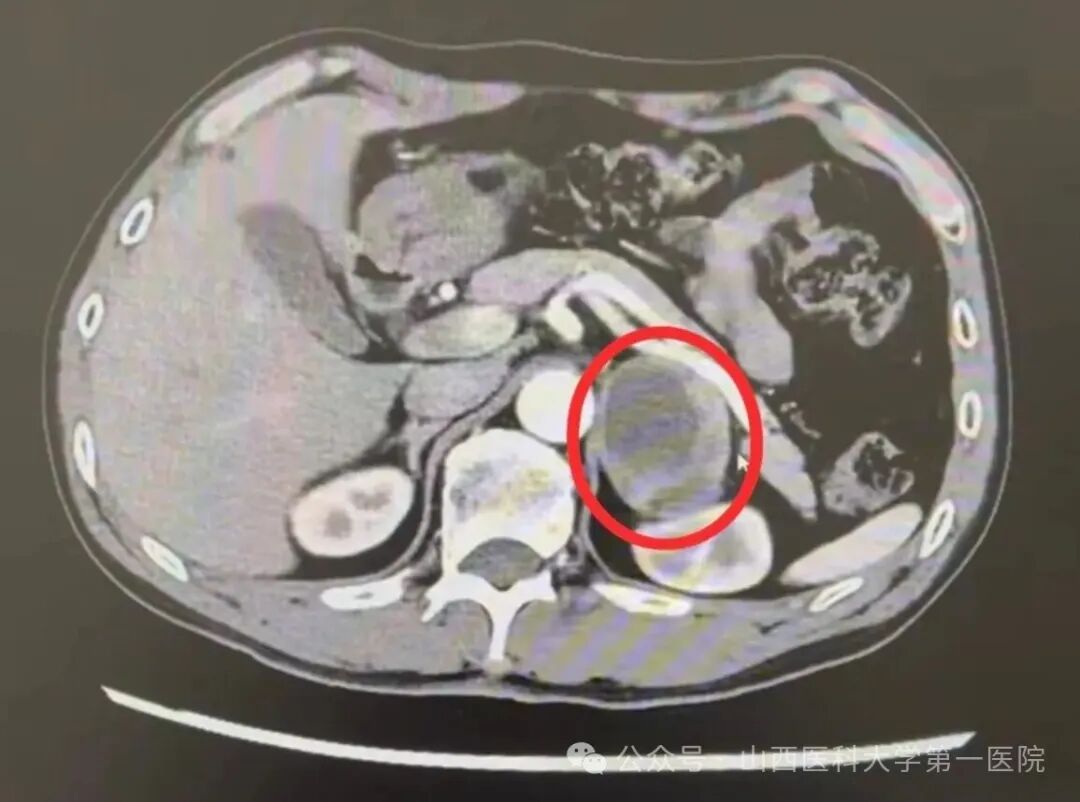

术前CT影像可见左侧肾上腺嗜铬细胞瘤病灶,红色圈内即为肿瘤病灶

本次帮扶诊疗活动在山医大一院泌尿外科曹晓明教授及麻醉科吕洁萍教授的全力支持下,由驻沁源县人民医院“千名医师下基层”刘凡主治医师具体协调,沁源县人民医院郝晋国院长统筹部署外科、麻醉科、手术室、心内科、重症医学科及医学影像科等多科室组成专项小组,为手术提供全方位保障。术前,原小斌、凡浙录与沁源县人民医院团队开展了多轮MDT研讨,结合患者CT影像提示的肿瘤体积较大(直径约6cm)、化验提示的儿茶酚胺激素分泌量成倍增高(甲氧基肾上腺素及甲氧基去甲肾上腺素高于正常上限4倍)以及合并有顽固性高血压、缺血缺氧性脑病等疑难复杂的疾病特点,共同制定了精细化手术前扩容准备方案以及个体化麻醉手术预案。